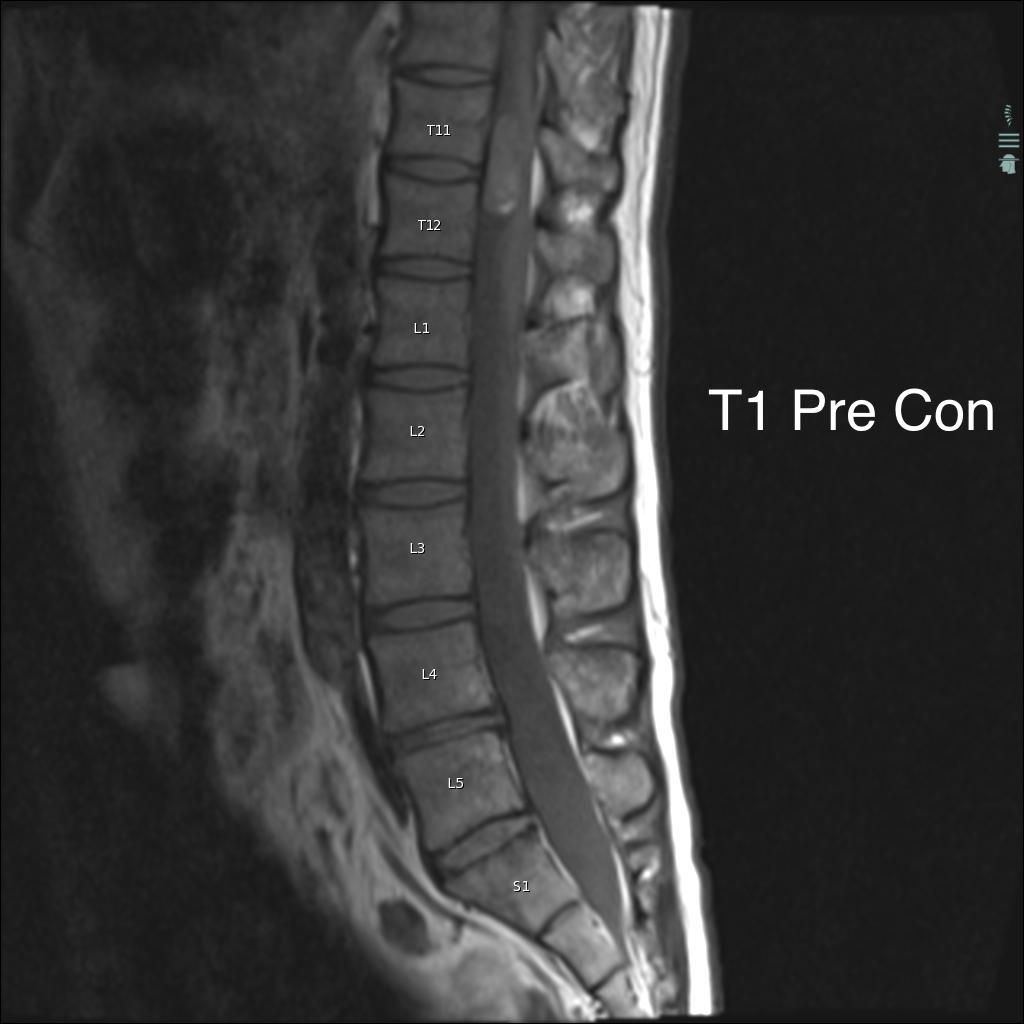

Can you diagnose this patient with low back pain, right lower extremity paraesthesias, and incontinence?

Case History: 40-year-old man with low back pain, right lower extremity paraesthesias, and incontinence. He presents 10 days later with worsening pain.

What is your diagnosis?